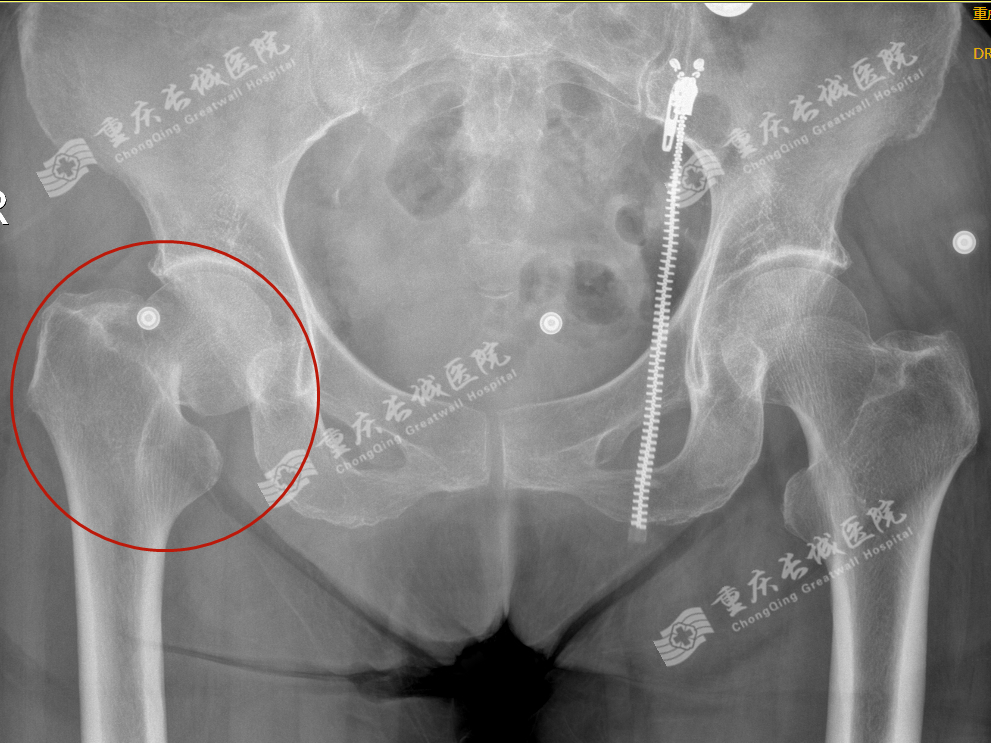

李嬢嬢就是属于此类情况,入院诊断为:右股骨颈骨折。

人工髋关节置换术是治疗股骨头坏死、髋关节发育不良、退变性髋骨关节炎、类风湿性关节炎等疾病终末期病变的最重要和最有效的手术之一。

人工股骨头置换创伤小、手术时间短、出血少、麻醉风险小,临床实用价值大。对于高龄、骨折前活动能力低、合并有多种疾病、全身情况较差的患者选择人工股骨头置换为佳。而双极人工股骨头在单极人工股骨头的基础上增加了一个摩擦界面,可提供更好的功能和活动范围,有利于减少髋臼关节面磨损,使术后疼痛、假体松动及下沉率减少。对身体条件较差的患者采用双极人工股骨头置换。随访中部分患者患髋有时会酸痛,但不影响关节活动,能满足老年人日常生活需要。全髋关节置换随着手术技术的提高,手术时间明显缩短,创伤减轻,且麻醉技术能及时处理手术并发症,手术风险明显降低。